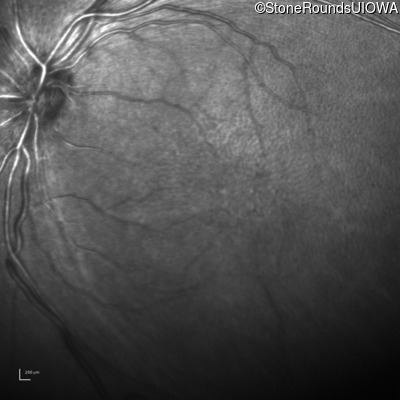

Infrared Fundus Photograph - Right - 10/40

Exemplar